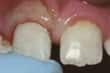

Parçası kopmuş ön dişler

Parçası kopmuş diş — Ağrı yoksa ve kopan parça küçükse ne zaman ve nasıl tedavi edileceğine karar vermek size kalmıştır. Kopan parçanın büyüklüğüne bağlı olarak düzeltilebilir veya kozmetik olarak düzeltilebilir. Diğer seçenekler arasında estetik kaplamalar, kuronlar ve dolgular yer almaktadır. Diş hekiminizden bu seçenekleri açıklamasını isteyin. Dolgu veya protez diş koparsa değiştirilmesi gerekmektedir.